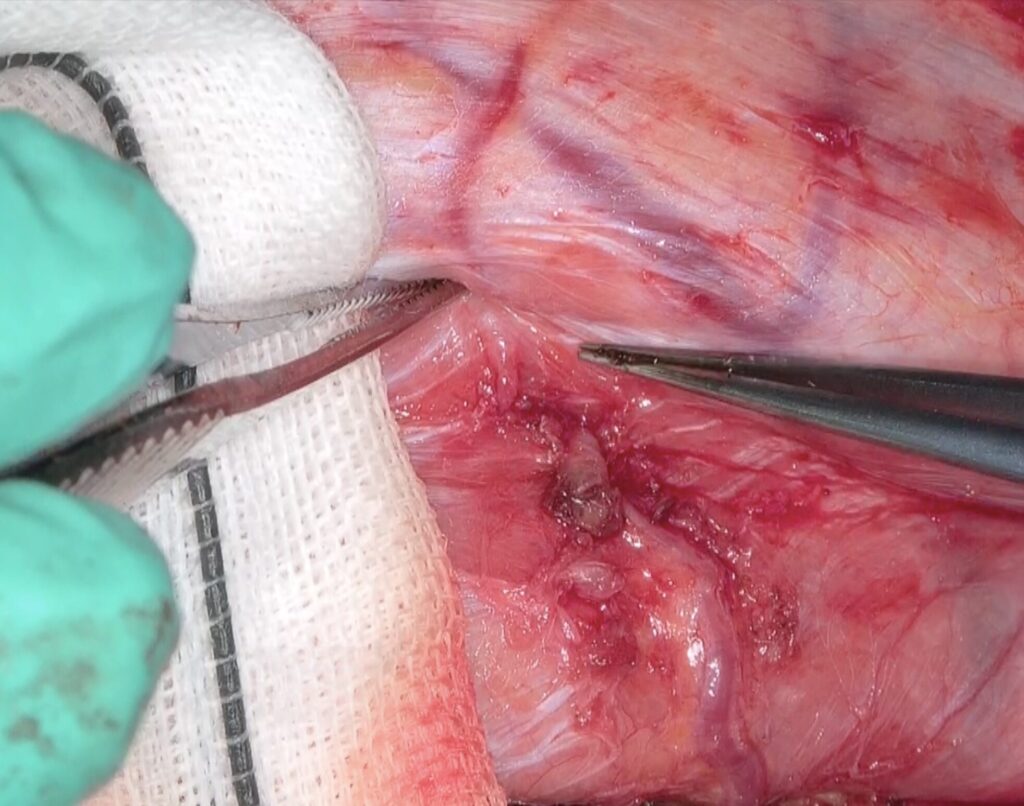

51歳女性の脳梗塞と脳室内出血を続けて起こした左片側もやもや病の患者さんをバイパス手術しました。STAがgaleaから外に出てGaleaの外に枝を出していたため皮弁翻展時にSTA頭頂枝が切れてしまい、端端吻合をしてからバイパスに用いました。2本とも無事開通しました。脳血流が著明に低下していたので術後の過灌流が心配で厳重な術後血圧管理を行いましたが、幸い順調な回復を見せています。

51歳女性の脳梗塞と脳室内出血を続けて起こした左片側もやもや病の患者さんをバイパス手術しました。STAがgaleaから外に出てGaleaの外に枝を出していたため皮弁翻展時にSTA頭頂枝が切れてしまい、端端吻合をしてからバイパスに用いました。2本とも無事開通しました。脳血流が著明に低下していたので術後の過灌流が心配で厳重な術後血圧管理を行いましたが、幸い順調な回復を見せています。